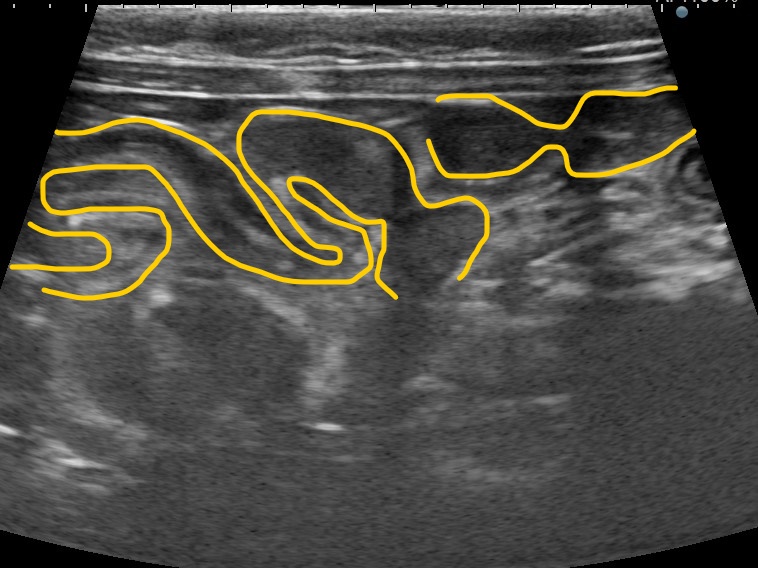

レントゲン検査およびエコー検査にて胃腸内にひも状異物が観察され、特徴的な腸管の蛇行(アコーディオン陰影)を認めました。

腸管のアコーディオン陰影像